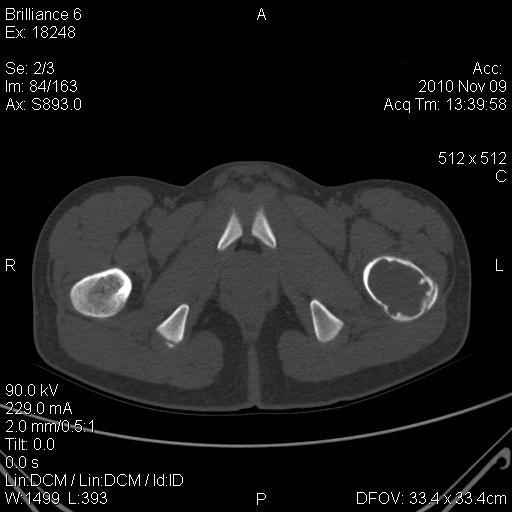

Мальчик 13 лет. В течение нескольких месяцев беспокоят боли в левом тазобедренном суставе.

При обследовании выявлена киста шейки левого бедра с сопутствующими изменениями в головке бедра, которые мы трактуем как дистрофические. Планируем вскрытие и санацию полости кисты передне-боковым доступом, костную пластику. Перед нами возникли следующие вопросы: для пластики использовать крыло подвздошной кости либо большеберцовую кость,либо их комбинацию, (полость большая,одним крылом можно не обойтись) или донорский аллотрансплантат с Коллапаном? Фиксировать ли? Если фиксировать, то чем? Доступны обычные угловые пластины либо АВФ.